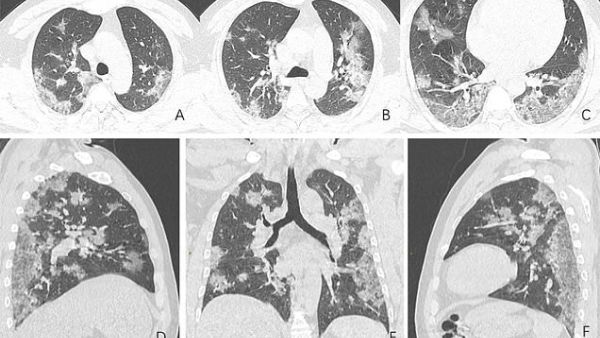

X-ray images and CT scans including those of a Chinese man, 44, who died from coronavirus show how the disease ravages its victims' lungs.

The scans show white patches in the lower corners of the lungs which indicates what radiologists call ground glass opacity - the partial filling of air spaces.

The shocking chest X-ray of one coronavirus victim, a 44-year-old man who worked at the Wuhan seafood market thought to be the origin of the outbreak, clearly show the ground glass opacity abnormality.

The scans, released by the Radiological Society of North America, show how the fluid in the spaces of the man's lungs became more pronounced over time, as evident when comparing image A to image F.

The man was admitted to hospital on December 25, 2019 after suffering from a fever and cough for almost two weeks. Doctors diagnosed the man with pneumonia and acute respiratory distress syndrome.

Despite being treated by doctors, he died a week later.